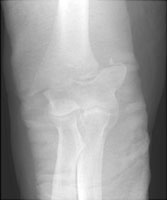

Supracondylar Fracture (Humerus)

Fractures of the distal humerus usually involve the supracondylar portion of the humerus and are extraarticular. Less common fractures of this region include transcondylar, bicondylar, and intercondylar fractures which involve the articular surface of the elbow (and are termed intraarticular). Volkmann's ischemic contracture (due to decreased blood supply) of the hand is a known complication of the supracondylar fracture. The supracondylar fracture is generally due to hyperextension injury due to a fall on an outstretched hand.

- Click on the image for a larger versionBAP radiograph of the elbow. The patient has sustained an obliquely oriented supracondylar fracture and has been placed in a cast.